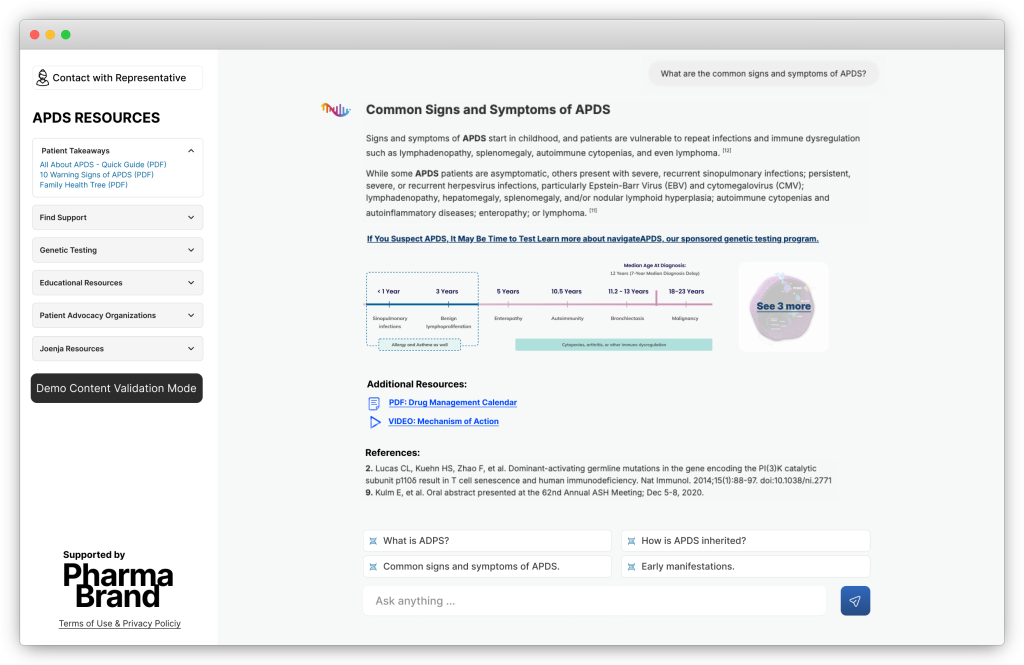

Disease Knowledge Hub – Web Prototype

Compliant AI Chat

A new format that speeds up physicians’ access to information – combining AI flexibility with fully approved, controlled content.

B.A.D.A.S. (Best Action Dynamic Activation System) is a breakthrough multi-agent system for pharmaceutical communication – a chat-based Brand Rep that merges compliant dialogue, actionable analytics, and instant brand orchestration.

It’s designed for pharmaceutical marketing teams seeking precision, compliance, and speed in every HCP interaction.